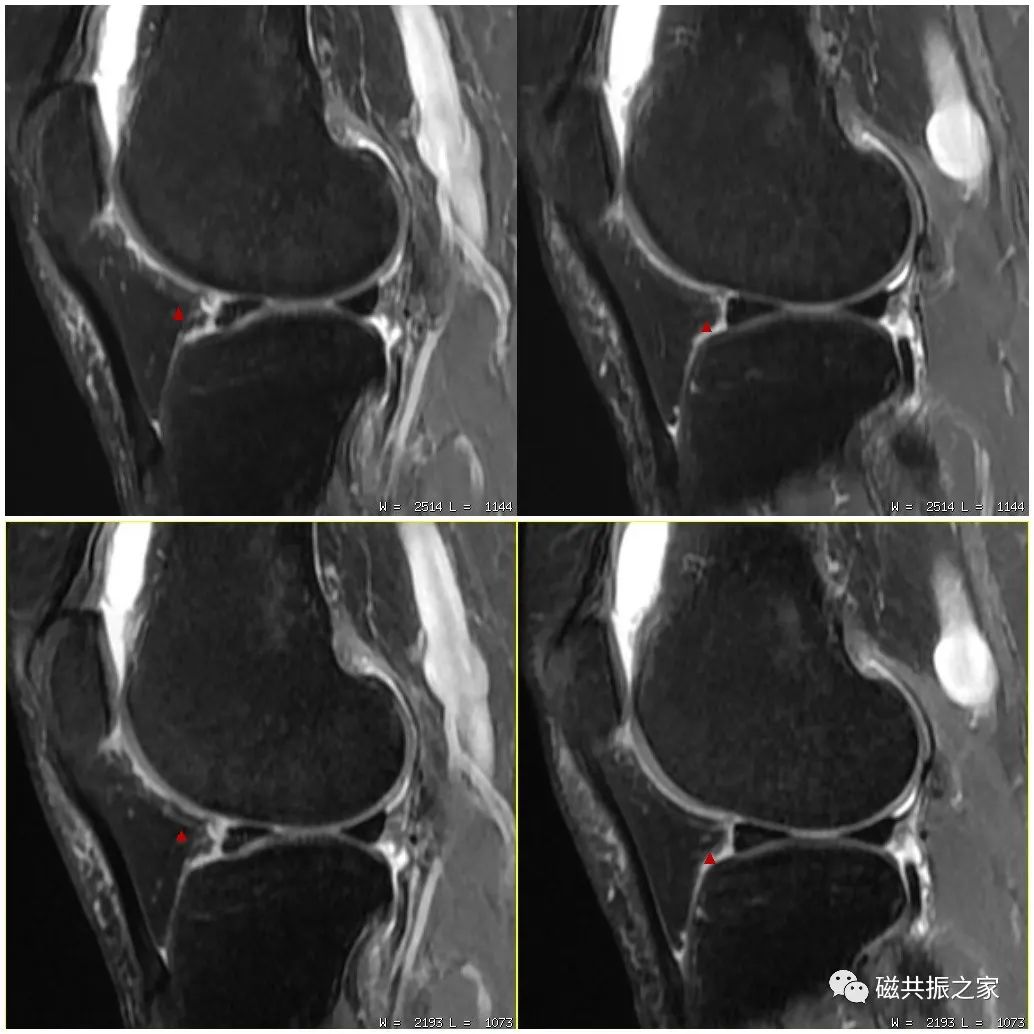

如图,上1,2幅图像为带宽12.5kHz;下1,2幅图像为带宽31.2kHz,(GE机型);虽然上两幅图像的信噪比比下两幅图像更高,但其分辨率明显不及带宽为31.2kHz的图像。

如图,上1,2,3幅图像的频率编码数为320;下1,2,3幅图像的频率编码数为512;虽然下面三幅图像的扫描体素较上面三幅图像更小,但其分辨率不及上面三幅图像。图像的分辨率并不是由单一参数决定的,在调整参数时应综合考虑时间、信噪比、对比度、伪影等相关因素。

如上图的压脂程度为80%,下图的压脂为100% 。我们知道MRI的信号主要来自于水和脂肪中的氢质子,虽然较强的压脂程度可突出某些组织间的对比,但更多的脂肪被抑制,图像的SNR会下降,则不利于我们做更高分辨率的图像。在小体素扫描时,使用部分压脂可以保证图像足够的信噪比。